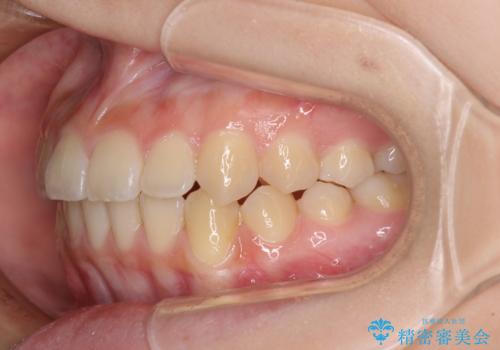

前歯のクロスバイト メタル装置での矯正治療

- 前歯のクロスバイトを気にして来院された患者様です。

前歯の叢生を解消するスペースを獲得するために上顎左右の親知らずを抜歯し、メタルブラケットにて矯正治療を行うこととしました。